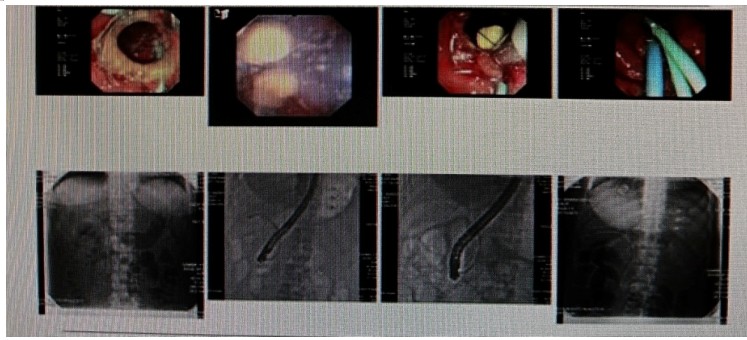

消化內(nèi)科肝病亞專科團(tuán)隊(duì)詳細(xì)討論,分析患者情況后,取消了周女士的肝穿刺活檢檢查,建議患者先行超聲胃鏡下膽胰掃查。在內(nèi)鏡醫(yī)師第三只眼——超聲胃鏡的掃查下,發(fā)現(xiàn)引起周女士肝功能受損的罪魁禍?zhǔn)?/span>原來是膽總管末端結(jié)石!伍友興主任醫(yī)師帶領(lǐng)團(tuán)隊(duì)給予患者行ERCP下取石后,周女士未再出現(xiàn)腹痛,肝功能恢復(fù)正常。

無獨(dú)有偶,劉先生也為反復(fù)出現(xiàn)肝功能受損到多家醫(yī)院就診檢查,未能找到原因,來到衡陽市中心醫(yī)院消化內(nèi)科就診,希望能在肝穿刺活檢下得出病因。在行肝穿刺活檢之前,醫(yī)生建議劉先生行超聲胃鏡膽胰掃查,發(fā)現(xiàn)引起劉先生反復(fù)肝功能受損原因,亦是膽總管結(jié)石引起,在ERCP術(shù)取石術(shù)后,患者肝功能恢復(fù)正常,未再出現(xiàn)異常情況。

張丹霞主任醫(yī)師介紹,超聲內(nèi)鏡通過胃十二指腸自然腔道,可以將探頭貼近相應(yīng)的位置,近距離的觀察胰腺及膽道系統(tǒng),準(zhǔn)確捕捉到直徑小于5毫米的胰腺異常病灶及膽道系統(tǒng)病灶。而體表B超常受皮膚、脂肪或腸道氣體干擾。CT或磁共振檢查只能提供靜態(tài)圖像,且對膽胰管陰性結(jié)石或是未引起明顯膽管梗阻性的結(jié)石檢查有局限性,因此對于有輕微腹痛合并肝功能受損的患者,建議常規(guī)行超聲胃鏡下膽胰掃查。超聲胃鏡、腹部彩超、腹部CT、腹部MRI同為診斷膽管細(xì)微病變的四架馬車,在膽總管結(jié)石診斷方面,超聲胃鏡膽胰掃查同ERCP一樣,是敏感性高、特異性強(qiáng)的診斷方法。超聲胃鏡發(fā)現(xiàn)可疑病變,可以完成穿刺活檢,還可行囊腫穿刺引流、膽管減壓、消融術(shù)等。